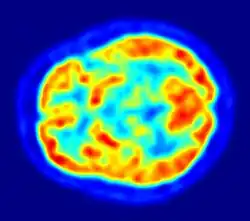

Although the human brain represents only 2% of the body weight, it receives 15% of the cardiac output, 20% of total body oxygen consumption, and 25% of total body glucose utilization.[138] The brain mostly uses glucose for energy, and deprivation of glucose, as can happen in hypoglycemia, can result in loss of consciousness.[139] The energy consumption of the brain does not vary greatly over time, but active regions of the cortex consume somewhat more energy than inactive regions, which forms the basis for the functional neuroimaging methods of PET and fMRI.[140] These techniques provide a three-dimensional image of metabolic activity.[141] A preliminary study showed that brain metabolic requirements in humans peak at about five years old.[142]

Imaging

Functional neuroimaging techniques show changes in brain activity that relate to the function of specific brain areas. One technique is functional magnetic resonance imaging (fMRI) which has the advantages over earlier methods of SPECT and PET of not needing the use of radioactive materials and of offering a higher resolution.[157] Another technique is functional near-infrared spectroscopy. These methods rely on the haemodynamic response that shows changes in brain activity in relation to changes in blood flow, useful in mapping functions to brain areas.[158] Resting state fMRI looks at the interaction of brain regions whilst the brain is not performing a specific task.[159] This is also used to show the default mode network.